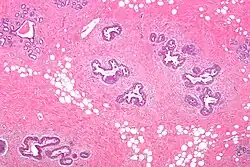

Histology

Early histological features expected to be seen on examination of gynecomastic tissue attained by fine-needle aspiration biopsy include the following: proliferation and lengthening of the ducts, an increase in connective tissue, an increase in inflammation, and swelling surrounding the ducts, and an increase in fibroblasts in the connective tissue.[26] Chronic gynecomastia may show different histological features such as increased connective tissue fibrosis, an increase in the number of ducts, less inflammation than in the acute stage of gynecomastia, increased subareolar fat, and hyalinization of the stroma.[24][26] When surgery is performed, the gland is routinely sent to the lab to confirm the presence of gynecomastia and to check for tumors under a microscope. The utility of pathologic examination of breast tissue removed from male adolescent gynecomastia patients has recently been questioned due to the rarity of breast cancer in this population.[57]